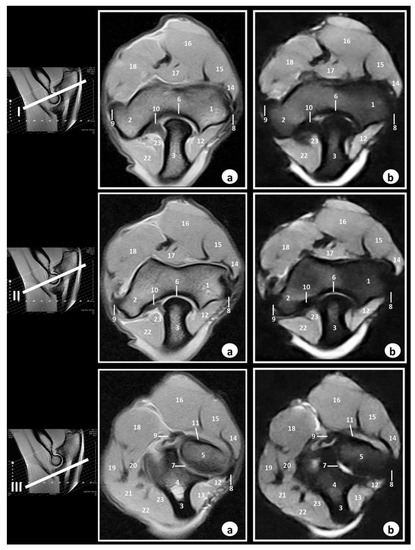

3.2. Magnetic Resonance Imaging